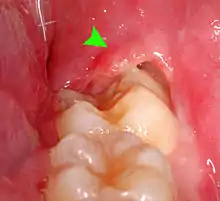

Pericoronitis is a common pathology of impacted third molar.[30] It is an acute localized infection of the tissue surrounding the impacted wisdom teeth. Clinically the tissue appears to be red, tender to touch and edematous. The common symptoms the patient’s report are pain ‘that ranges from dull to throbbing to intense’ and often radiates to mouth, ear or floor of the mouth. Moreover, swelling of the cheek, halitosis and trismus can occur.[31]